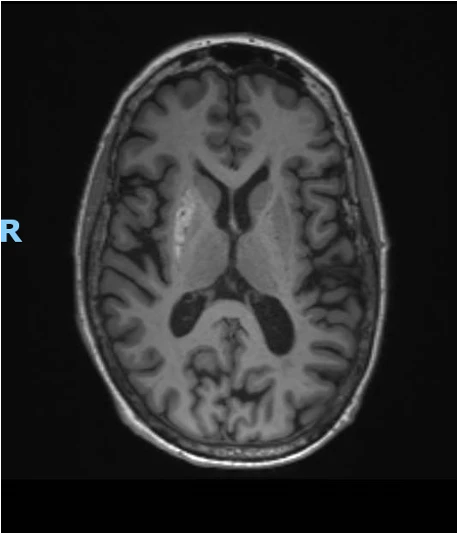

L’IRM démontre une lésion mal délimitée, en hypersignal spontané T1 (cf image ci-dessous), en hyposignal T2, en contour de géographie, s’étendant à hauteur du putamen droit, sans prise de contraste, sans restriction de la diffusion.